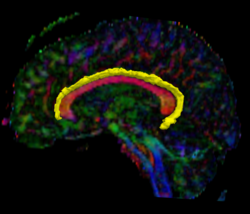

Recently, we have applied this method to the cingulum bundle, as shown in the following images:

Fig 1. Cingulum Bundle Anchor Tracts

Detailed View of the Cingulum Bundle Anchor Tract